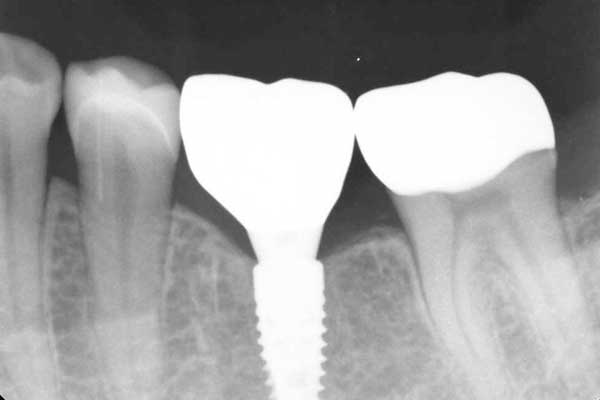

④ インプラント治療

治療中

治療後

年代・性別

70代・男性

歯が折れた

治療内容

抜歯を行い、その後インプラント治療を行い新しく歯をつくりました。

治療期間・回数

8ヶ月

費用

約60万円(税込)

リスク・副作用

処置の際には様々な合併症が起こることがあります。